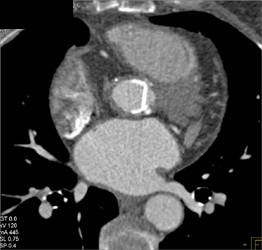

Aortic Valve Replacement